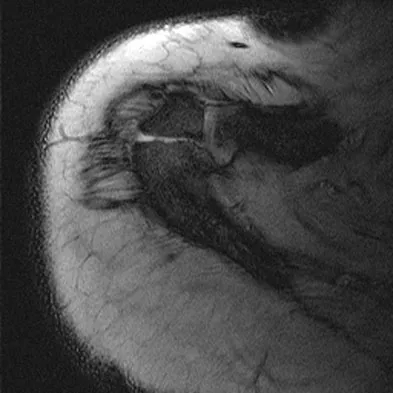

A 23-year-old man reports pain on the superior aspect of his right shoulder with repetitive overhead activities and when lying on his right side. Figure 29 shows an axial MRI scan. What is the most likely diagnosis based on the MRI findings?

Explanation